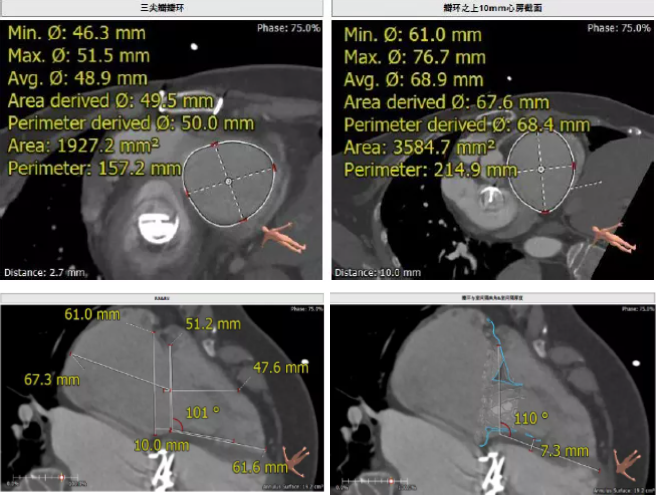

患者64歲女性,18年前接受了“正中開胸二尖瓣機(jī)械瓣置換術(shù)”,2年前超聲檢查發(fā)現(xiàn)“三尖瓣重度返流”。輾轉(zhuǎn)多地,嘗試各種治療方式,均無明顯改善。由于存在相關(guān)合并癥,傳統(tǒng)外科手術(shù)風(fēng)險(xiǎn)大,郭惠明教授團(tuán)隊(duì)結(jié)合該患者CT、超聲檢查結(jié)果,對該患者的情況進(jìn)行了充分的評估和討論,決定采用LuX-Valve人工三尖瓣介入瓣膜置換系統(tǒng)對患者進(jìn)行微創(chuàng)介入治療,以最小的創(chuàng)傷解決患者的病痛。

術(shù)前CT評估